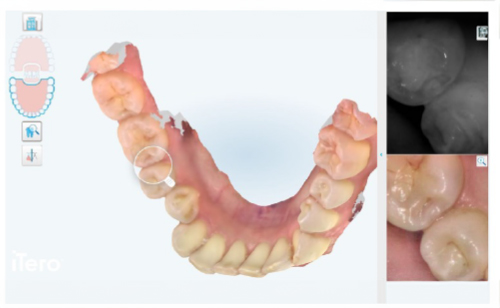

口腔内をスキャンする機械を用いて、歯の本数、虫歯の有無、詰め物の状態を3次元的に検査・記録します。

その後、歯科医師により直接確認を行います。

口腔内スキャンを用いて、虫歯のチェックや歯の汚れを染め出してチェックします。

虫歯の精密検査を行う際は染め出しをせず口腔内スキャンを行う場合もあります。